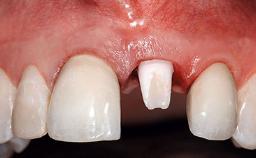

A healthy 28-year-old female patient presented for a consultation on treatment options to restore her upper right central incisor. At the clinical examination, the tooth responded to percussion and palpation. The gingiva was red and slightly swollen, with a mid-facial probing depth of 10 mm. The upper right lateral incisor showed no signs or symptoms, did not respond to exploration and percussion, and the vitality test was positive. The periapical radiograph revealed that tooth 11 had been endodontically treated, with no lesion evident at the apex. A small radiopaque calcified structure surrounded by a narrow radiolucent zone (3 × 3 mm) was present at the apex of tooth 12.